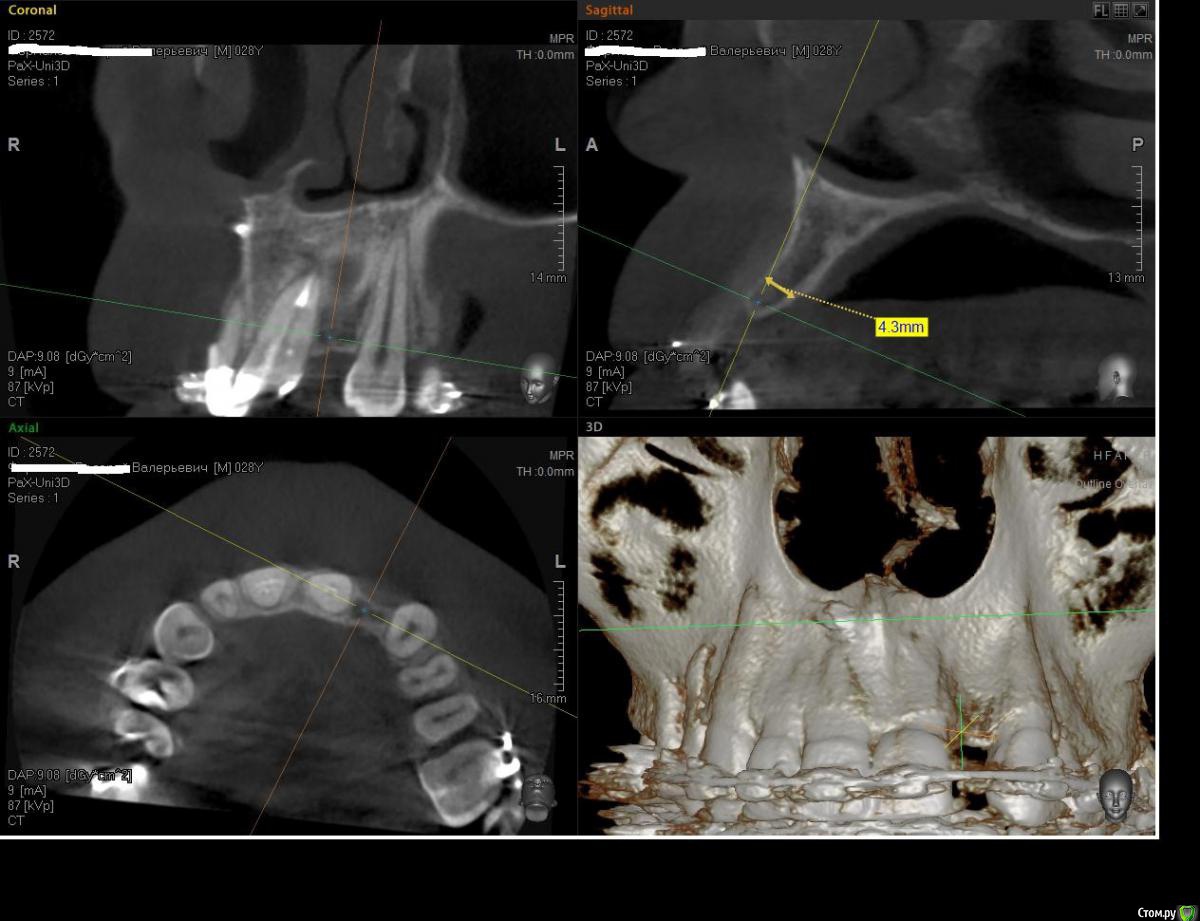

Kostoprav Опубликовано 8 июля, 2015 Поделиться Опубликовано 8 июля, 2015 ИЗНАЧАЛЬНАЯ СИТУАЦИЯ ПОЛУЧИЛОСЬ сори что нет фото до имплантации. Блок взял с тела челюсти, фиксировал двумя винтами (во время имплантации выкрутил только один), присыпал gen os, укрыл дермой-получил заметный прирост слизистой) имплант альфадент 3,75х11,5 2 Ссылка на комментарий

Kostoprav Опубликовано 8 июля, 2015 Автор Поделиться Опубликовано 8 июля, 2015 Видно что блок прирос. ЗдоровоОстальное оценить сложноМне нравится положение импланта в плане оси.Но уровень заглубления не ясенТакже не видно прироста десныВ общем мало данных для оценкиНо опять же вам именно она и нужна?по вестибюлярной поверхности заглубил приблизительно на 1мм с небной больше получилось. слизистая по сравнению с первым разом значительно толще стала, доказать к сожалению не могу так как не делал фото(: я выложил этот пост не только ради оценки, может кому из начинающих данный случай сгодиться 3 Ссылка на комментарий

Kostoprav Опубликовано 28 июля, 2015 Автор Поделиться Опубликовано 28 июля, 2015 Сколько времени прошло после фиксации блока? Чем забирает е блок? на момент имплантации 6 мес. забор блока делал линденманом Ссылка на комментарий